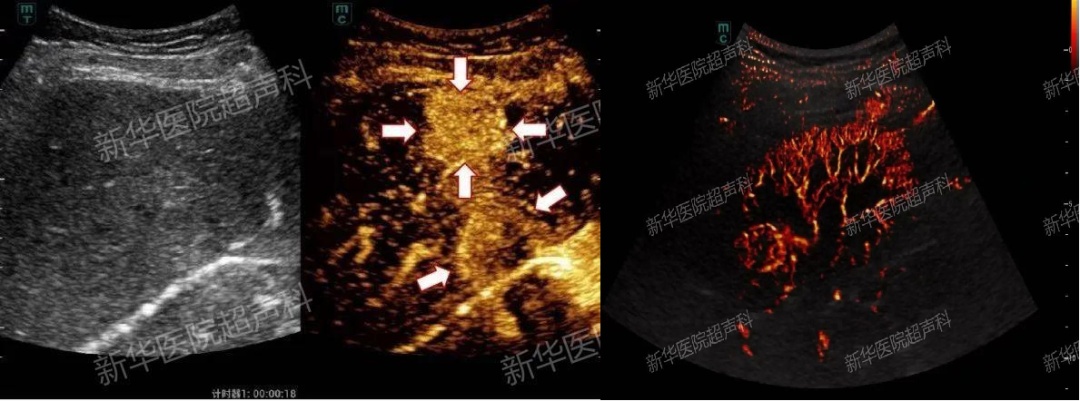

精准诊断:如果将超声比作“黑白电视机”,那超声造影就像是“高清彩色大电视”。

虽然超声造影听起来很高大上,但其实原理非常简单:就是在常规超声的基础上,通过肘静脉注射一种特殊的超声造影剂,它们就像一个个“小气球”,随着血液流动,来增强人体的血流信号,通过实时动态观察病灶或血管内微循环血流灌注,提供比常规的超声更丰富、更明确的诊断信息,提高对病变的检出率并对病灶良恶性进行更精准的鉴别。

上海新华医院超声科依托新华医院儿科临床学科特色,在国内率先开设儿童肿瘤专科门诊,应用高分辨超声造影、超微血流超声成像、超声剪切波弹性成像、超声脂肪肝声衰减定量、三维超声、超声与CT/ MRI/PET-CT等多模态影像融合导航等技术,大大提高了疑难病例的诊治水平,让患儿得到及时精准的诊断。